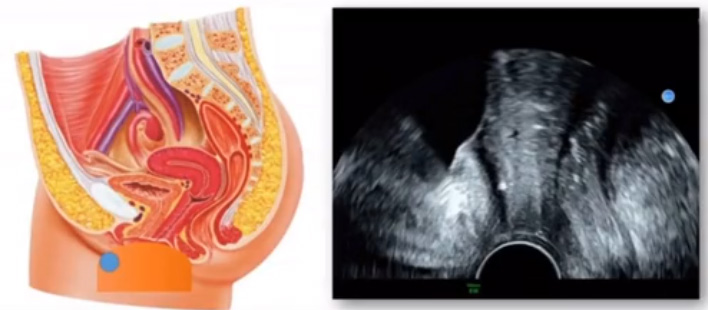

位于输卵管的后下方,子宫两侧的后上方;借卵巢系膜与子宫阔韧带后层相连。正常成人卵巢约4x3x2cm,跟睾丸的数值差不多,都是性器官,绝经后卵巢萎缩变小、变硬。所以绝经后妇女很难找到卵巢,主要功能:生殖和内分泌功能分泌性激素。女性的第二性征。女性内生殖器的血管分布,动脉有子宫动脉,卵巢动脉,阴道动脉,阴部内动脉。静脉它是与动脉伴行。重要了解的是子宫动脉,子宫动脉是髂内动脉前干的重要分支,妊娠时候血流速度会增加的,为无创性检查胎盘血管阻力的方法。未孕期频谱为高阻力低舒张波形;正常妊娠时血流速度增加,血流阻力下降。